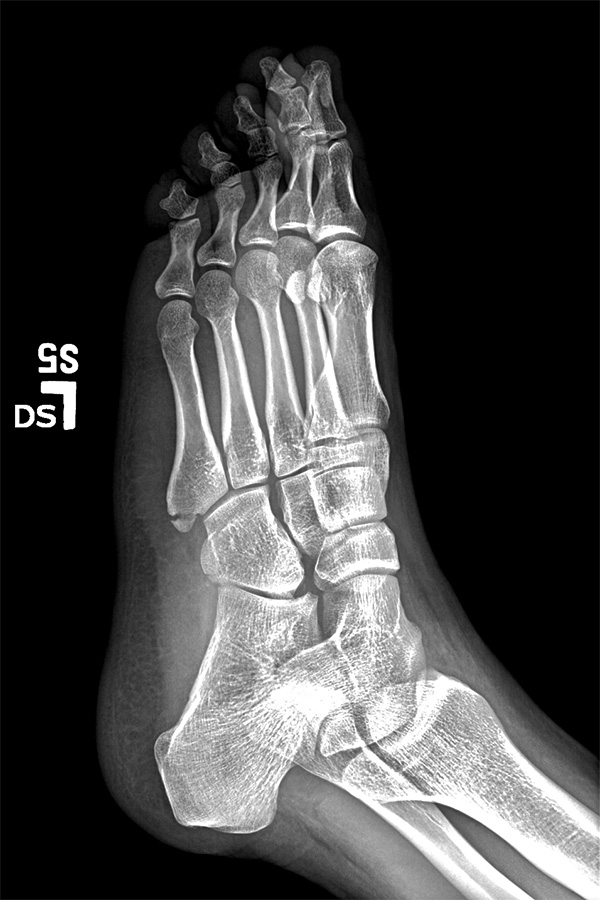

i had nothing to lose and was curious to get my hands on my broken foot x-rays from last year 2 years ago, so i went to the sub-basement of the bigelow building. i wasn't sure if i could get it today, and i wasn't sure if i had to pay. the man who helped me said he'd put everything onto a disc, and that he could do it while i waited. what i thought would be a quick wait ended up being almost 45 minutes. the big hold up were the MRI scans, which i already had a copy. was he downloading the images via 1990's modem technology? i also learned that if you request the images for personal use then you'd have to pay, but it's not seriously enforced, and if you just make up a doctor, you can get everything for free (they give you the disc anyway, they don't mail it out).